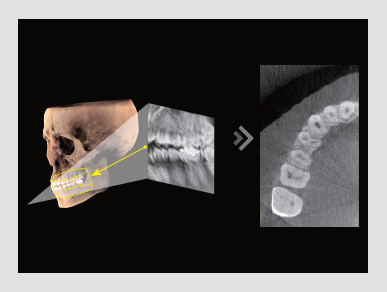

El innovador FOV proporciona un volumen en forma de arco que muestra una vista más amplia de la dentición en comparación con otros dispositivos del mismo FOV.

Normalmente, una imagen de 10x8.5 muestra el diente No.8. Sin embargo, cuando los terceros molares están tumbados sobre su lado hay una gran posibilidad de que el diente se corte de la imagen.

El “volumen en forma de arco” elimina esta posibilidad y muestra el área de dentición oculto.